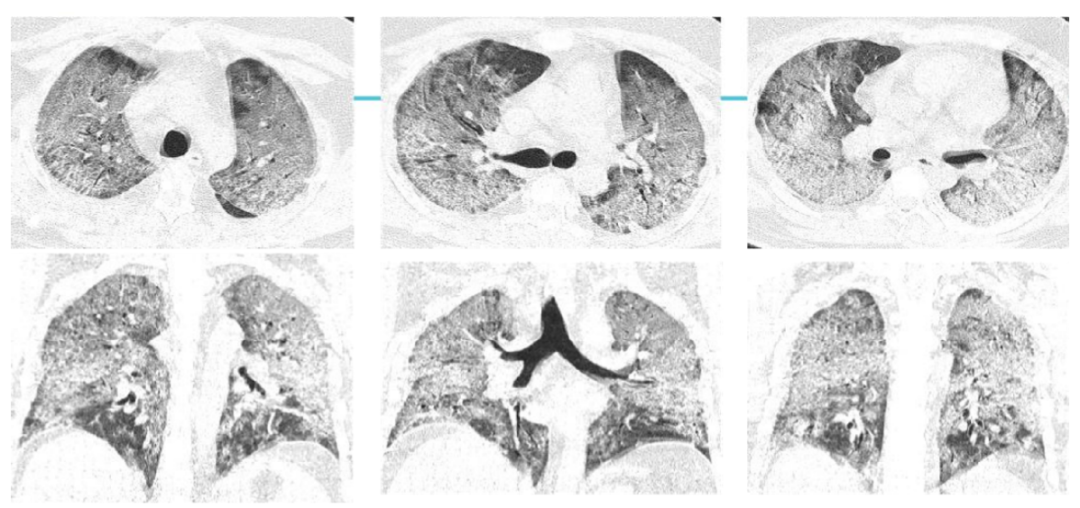

案例三,30歲,男性,確診病例

胸片顯示雙肺彌漫性病變

影像所見:發(fā)熱12天,胸悶、氣喘7天。胸部CT顯示兩肺彌散性磨玻璃影,呈“白肺”改變,其內可見空氣支氣管征、雙側膈面上抬。

從這3個確診新冠肺炎呈“白肺”病例來看,“白肺”多見于老人、兒童以及帶有基礎病的新冠患者,病灶可發(fā)生在肺內任何肺葉,病灶形態(tài)特點也是多樣化,符合病毒性肺炎的影像表現(xiàn)。從影像學角度出發(fā)重點在于快速評估病情,提升人工讀片的客觀性。 “啄醫(yī)生閱片機器人??新冠肺炎CT影像輔助分診與評估系統(tǒng)”可以準確地識別新冠肺炎的典型影像表現(xiàn)如雙肺外周胸膜下多發(fā)的磨玻璃影、小葉間隔增厚或合并鋪路石征等,對于部分患者由于影像表現(xiàn)早于臨床癥狀,更具有早期發(fā)現(xiàn)、早期診斷的優(yōu)勢。